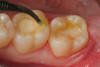

Fig 7. An occlusal view of the completed composite restoration of tooth No. 13.

Figure 7